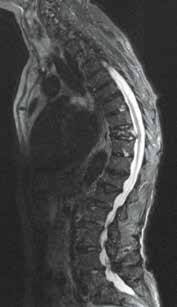

Osteoporotische Sinterungsfrakturen treten in Deutschland mit zunehmender Häufigkeit auf. Vergesellschaftet damit sind eine erhöhte Morbidität und Mortalität. Die epidemiologischen Daten dazu zeigen klar die daraus resultierenden Probleme wie einen erhöhten Medikamentenbedarf, vermehrte Krankenhausaufenthalte, Depression, soziale Isolierung und eine erhöhte 5‑Jahres-Mortalität. Frakturen und daraus resultierende Fehlstellungen begünstigen Anschlussfrakturen. Eine Abhängigkeit von der Knochendichte besteht insofern, als niedrige Werte im T‑Score das Risiko verstärken. Kyphoseassoziierte Fehlstellungen scheinen das Risiko ebenso zu erhöhen. Osteoporosebedingte Gestaltveränderungen gelten heute als häufigste Ursache relevanter adulter Deformitäten der Wirbelsäule (Abb. 1) 1 2.